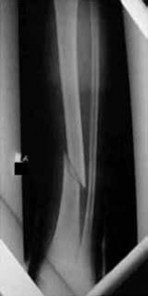

Figure 29Figure 29 is the radiograph of a 30-year-old man who sustained an isolated tibial shaft fracture. What is the most common deformity with nonsurgical management?